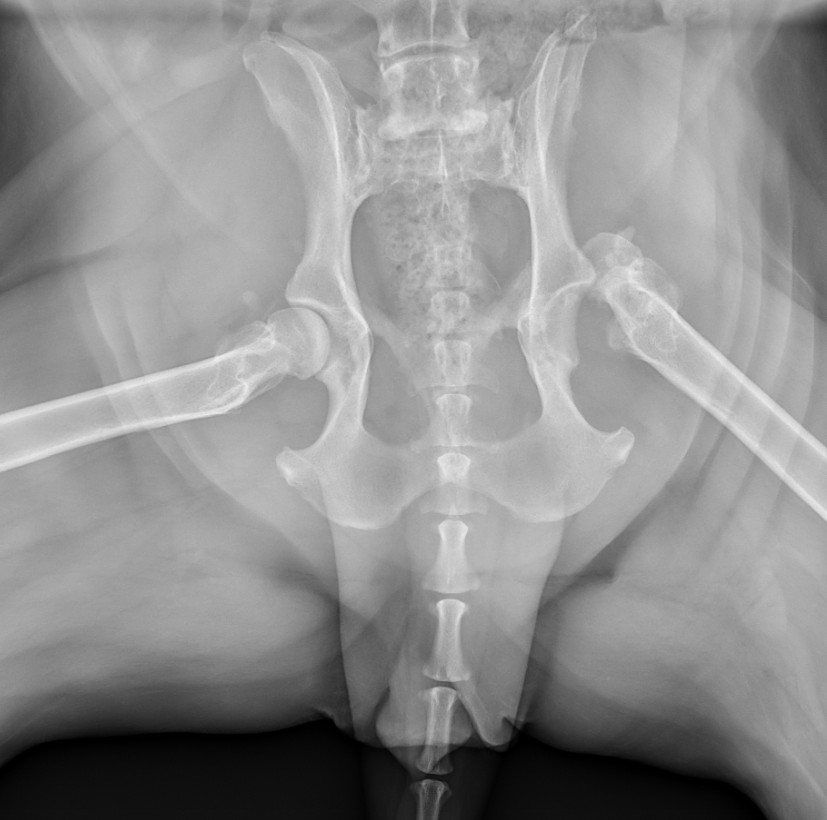

Abby's lifelong struggle with joint pain, from the trauma she's endured, began manifesting dramatically a few years ago when she tore both of her CCLs (cruciate ligaments), a year apart, requiring two separate surgeries. Unfortunately, the second surgery was not successful, leaving her with chronic instability. To manage the resulting pain, her medication regimen has gradually increased until she recently reached the maximum safe pain regimen her vet is comfortable giving her including Gabapentin, Galliprant, Librela, and Amantadine while she also receives treatment for her anxiety and hypothyroidism (a condition that contributed to her weight, which her vet and I are managing with medication and diet changes). The Need Abby's hip joint has suffered a Cranial Dorsal Luxation (a severe dislocation), meaning the top of her femur is grinding painfully on top of the hip socket.

X-Ray taken December 1 at Ohio State University Veterinary Clinic

Because her current, maxed-out medication cocktail is still not enough to control this relentless pain, the specialists at OSU Veterinary College have determined that this luxation cannot be fixed by any other means than definitive surgery.

Our options are either an FHO (where they cut off the head of the femur and allow scar tissue to become a floating joint) or the preferred, yet costly, Total Hip Replacement (THR). The FHO isn't reccomend for dogs over 70lbs. Even when Abby loses more weight, she'll never be that light.